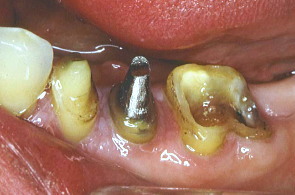

歯冠がないところにはポスト(芯)を入れる。左がプラスチック、右はそれを鋳型にして金属にしたもの。

製作した鋳型を口腔内の歯牙に入れ、レントゲンを撮り適合を検査する。

下顎の歯牙にも同じようなものを作りレントゲンで根っこを検査した。

分割式のプラスチックのポスト(芯)を作製。赤いものがプラスティック、黒が金属のポスト(芯)。

金属のポストを歯牙に装着したところ。レントゲンでその適合をチェック。結果はgood!!

金属のポストに仮り歯をかぶせたところ。  ~今後は石膏歯牙模型を作り、クラウン等の上物製作に入る。